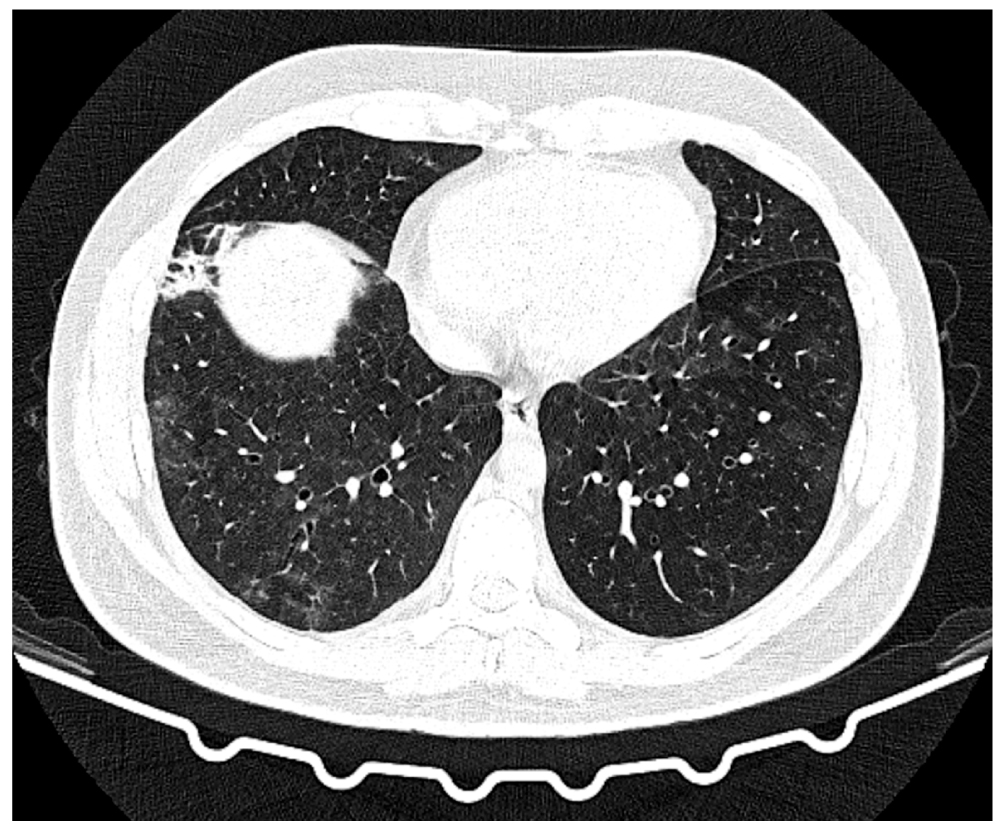

Fig. 1. Axial sections at the level of the aortic arch, pulmonary window. Changes in the areas of heterogeneous infiltration: a: chest CT scan dated July 15, 2022, day 11 of the disease, day 1 of hospitalization; b: chest CT scan dated July 22, 2022, day 18 of the disease, day 7 of hospitalization; c: chest CT scan dated August 3, 2022, day 30 of the disease, day 19 of hospitalization; d: chest CT scan dated August 9, 2022, day 36 of the disease, day 25 of hospitalization.

On day 18 of the disease and day 7 of the hospital stay, the chest CT scan dated July 22, 2022 (Fig. 1b, 2b, 3b) revealed negative changes in bilateral multifocal pneumonia and weakly negative changes in bilateral pneumothorax and hydropericardium. Moderate intrathoracic lymphadenopathy without changes and a focal mass in the left breast were observed. Antibiotic therapy was re-adjusted; rifampicin was discontinued, and intravenous tigecycline 100 mg daily was added to levofloxacin 1 g daily. This regimen demonstrated gradual positive changes.

On August 10, 2022 (day 37 of the disease, day 26 of hospitalization), the patient’s condition was deemed satisfactory. The patient reported a rare dry cough and slight exertional dyspnea. The patient’s air saturation was 97%. The chest CT scan dated August 9, 2022 (Fig. 1d, 2d, 3d) demonstrated positive changes in bilateral multifocal pneumonia, with a decrease in intensity. Additionally, there were no changes in cavitary lesions in the right lung, which could be attributed to dilated bronchial lumen or heterogeneous infiltration. Hydropericardium also showed positive changes.